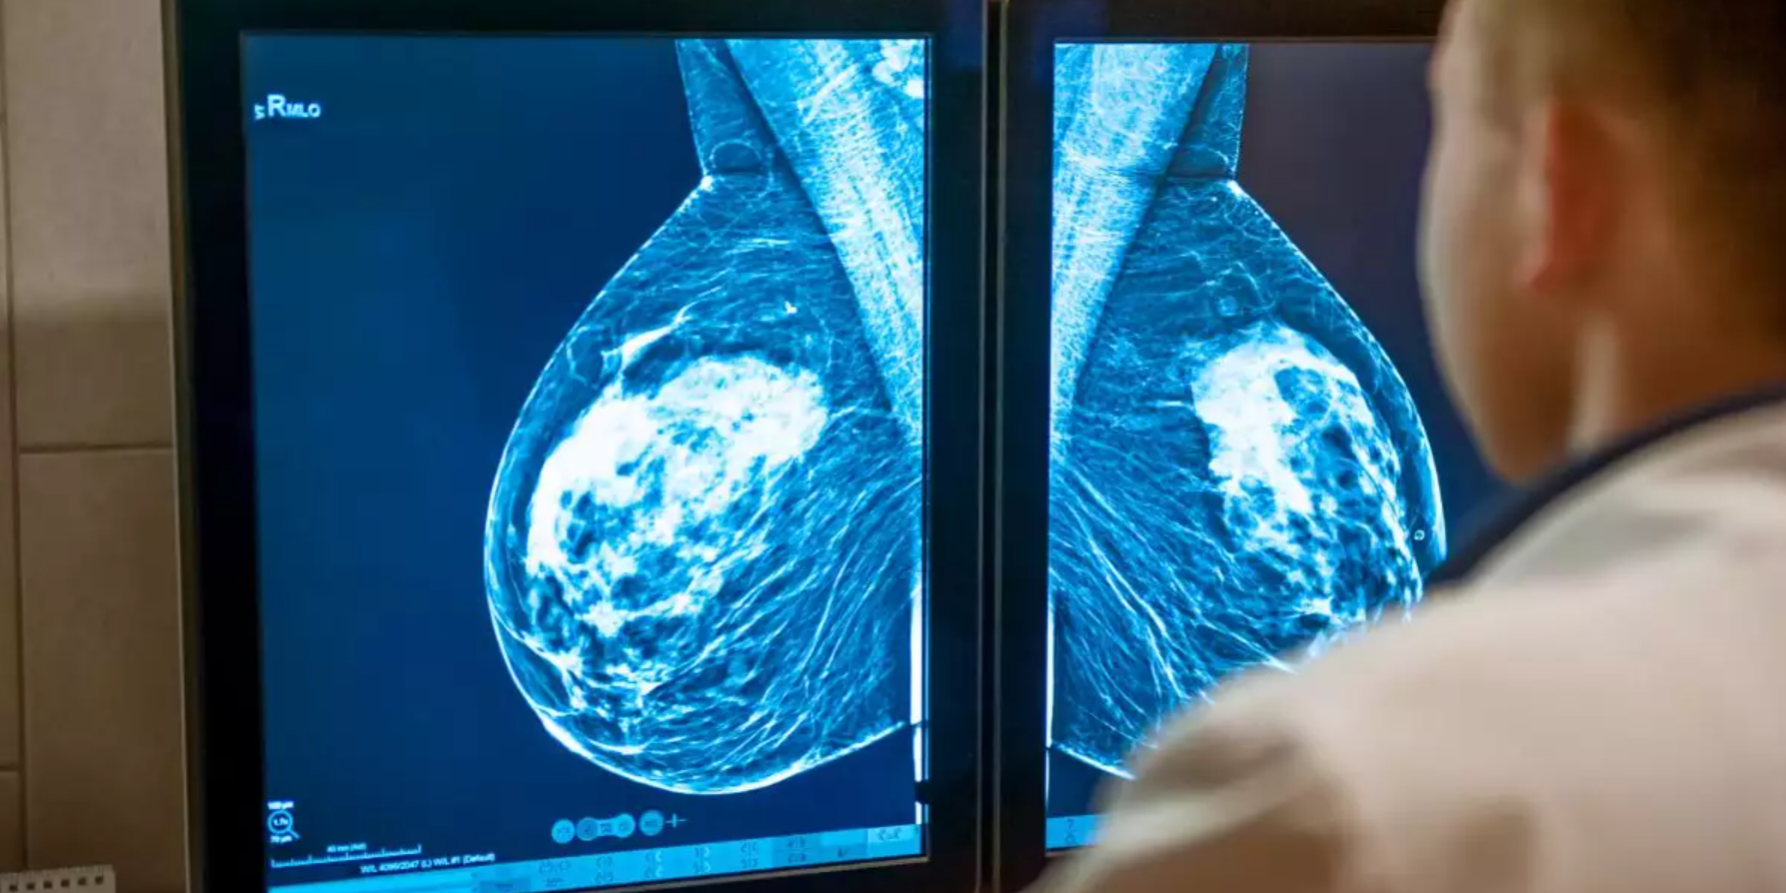

Cinco pesquisadores da FHI, da Universidade da Califórnia e da Universidade de Washington tiveram acesso a um programa de IA disponível comercialmente para analisar retroativamente as mamografias de 116.495 mulheres que participaram de um programa de detecção norueguês entre 2004 e 2018. No total, 1.607 mulheres desenvolveram câncer de mama.

O algoritmo foi capaz de prever quais mulheres corriam maior risco de desenvolver câncer de mama e até mesmo identificar qual mama estava em risco, quatro a seis anos antes do diagnóstico.

“Observamos que a mama que desenvolveu câncer tinha uma pontuação de IA cerca de duas vezes maior que a outra mama. O estudo mostra que os algoritmos de IA já disponíveis no mercado podem ser usados para desenvolver programas de detecção mais personalizados”, disse Solveig Hofvind, que lidera o programa de detecção e o projeto de IA.